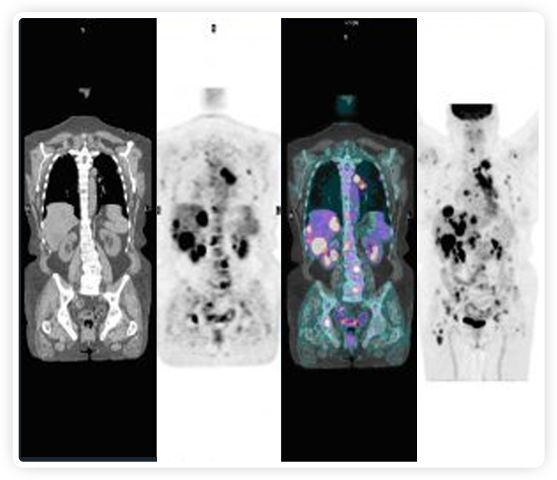

到目前為止,放射腫瘤學(xué)中(使用的圖像主要是結(jié)構(gòu)性的,而PET圖像可以提供生物學(xué)信息。通過使用注射示蹤劑,例如18-FDG,PET可以描繪腫瘤的代謝活性,使其“點亮”。(FDG是用于可視化癌癥代謝的最廣泛使用的示蹤劑。與正常組織相比,腫瘤細胞保留更高水平的FDG。)不同的PET示蹤劑可以識別腫瘤的不同生物學(xué)特征,例如特定生物標(biāo)志物抗原(例如,PSMA)或甚至探測免疫系統(tǒng)本身(例如,PDL1表達或活化的T細胞)。

RefleXion將PET成像與立體定向放射治療相結(jié)合。在注射示蹤劑后,RefleXion的技術(shù)基于示蹤劑信號實時地在一個或多個目標(biāo)上引導(dǎo)治療性X射線。使用這種專有方法,RefleXion的平臺有可能比現(xiàn)有系統(tǒng)向癌癥病變提供更高劑量的輻射,并改善周圍健康組織的保護。

為了避免PET長圖像采集時間,RefleXion開發(fā)了一項專利技術(shù)使用重合的PET光子對來指導(dǎo)放射治療束,因為實時檢測發(fā)射的光子,為生物指導(dǎo)提供了一種時間有效的方法。